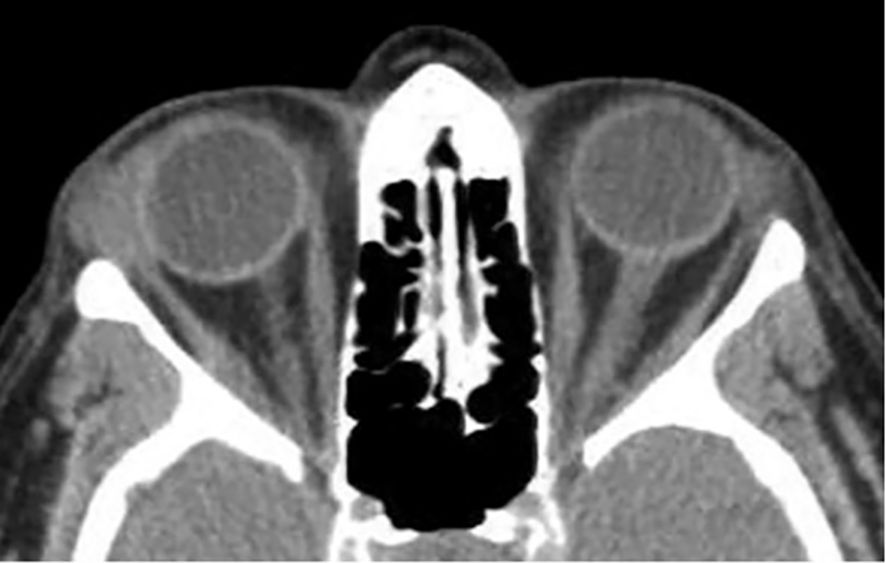

Orbital masses include a diverse spectrum of benign, malignant, inflammatory, and vascular lesions in pediatric and adult patients. Accurately diagnosing the type of lesion is critical, as management strategies differ significantly. Advanced imaging is therefore essential, and computed tomography (CT) is central to orbital evaluation. We reviewed the literature to synthesize evidence on CT features across common orbital pathologies and correlated imaging with clinical presentation to emphasize diagnostic relevance. CT characteristics are summarized for vascular lesions (cavernous venous malformation, lymphatic malformation), inflammatory conditions (orbital myositis, dacryoadenitis), benign lesions (dermoid cyst, pleomorphic adenoma), and malignant lesions (lacrimal gland lymphoma, adenoid cystic carcinoma, rhabdomyosarcoma). We present characteristic patterns of location, morphology, enhancement, and bone change, with practical discriminators and common pitfalls to aid differentiation. When used alongside clinical context, CT remains a preferred modality in many clinical settings due to its rapid acquisition, wide availability, and reliable depiction of bone and calcifications. It supports accurate diagnosis and informed management decisions in time-critical settings. This review provides a structured reference for interpreting CT findings across a wide range of orbital disease.